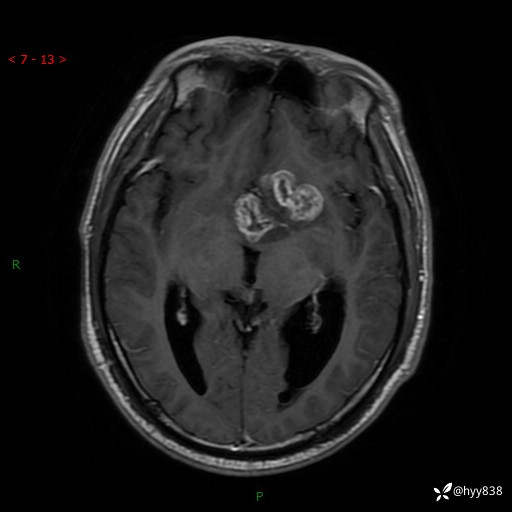

颅脑MRI平扫+增强